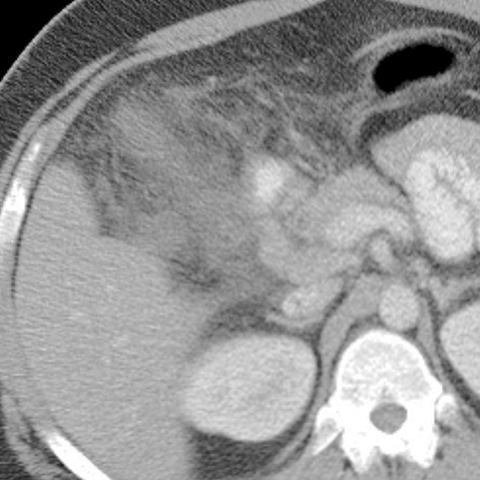

67-year-old diabetic male with a long history of colicky RUQ pain presents with a sudden onset of increased abdominal pain. [2 of 2]